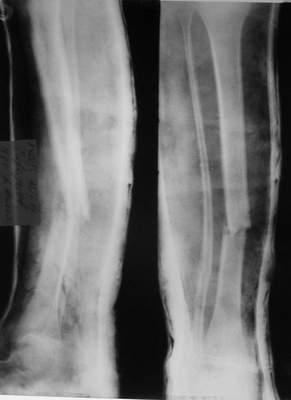

Ребенок 12 лет, поступил после падения с высоты примерно 2,5м.

Перелом костей н\3 правой голени со смещением. Перелом большеберцовой кости можно охарактеризовать как компрессионно-оскольчатый.

Скелетное вытяжение за пяточную кость.

В первые сутки значительный отек с\3, н\3голени, стопы с развитием практически неуловимого в нашей стране ;) компартмент синдрома (фасциотомии не проводилось), недочеты по укладке на скелетном

вытяжении.

Формирование некроза кожи по задней поверхности н\3 голени~ 1 %, вторичное заживление, кожная пластика. Нейропатия м\берцового нерва (отсутствие активного разгибания 1 пальца) На вытяжении около 8 нед, в дальнейшем в гипсовых повязках ~ 8 мес.